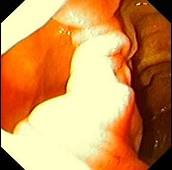

问题 女性,45岁。腹部饱胀不适2年余。表情自然,皮肤无黄染,未见蜘蛛痣,巩膜无黄染。腹平坦,腹肌软,全腹无压痛反跳痛,肝脾肋缘下0.5cm,胃镜检查如下图,诊断为 ( )

选项 A、十二指肠穿孔 B、十二指肠雍滞症 C、十二指肠溃疡 D、十二指肠炎 E、十二指肠憩室

答案 E